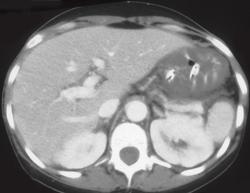

Gastric Varices (dual Phase- Seen Best in Portal Phase)